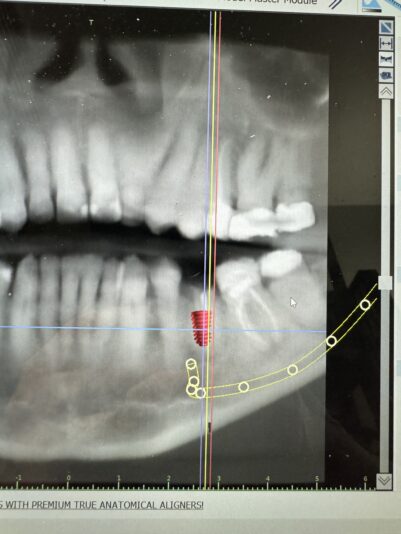

#20 is planned for an extraction and socket grafting. I planned for an implant 4.0x7mm (which I’m thinking is a bit short – would have liked at least 8.5mm) but is limited in length due to the lingual concavity.

The implant fits into this pre-extraction dimensions; however, I’m anticipating some bone loss even after socket grafting and am concerned that there will be inadequate bone for my 4x7mm implant.

It looks like there’s great interproximal Bone so that’s what you should lean into on a case like this. You may have to go slightly wider to get really good engagement on the mesial and distal walls and remove some of the lingual portion of the bone socket just slightly so that you can maintain a good 2 mm buccal gap so you have sufficient bone around the implant and you’ll not have to worry about a ridge augmentation.